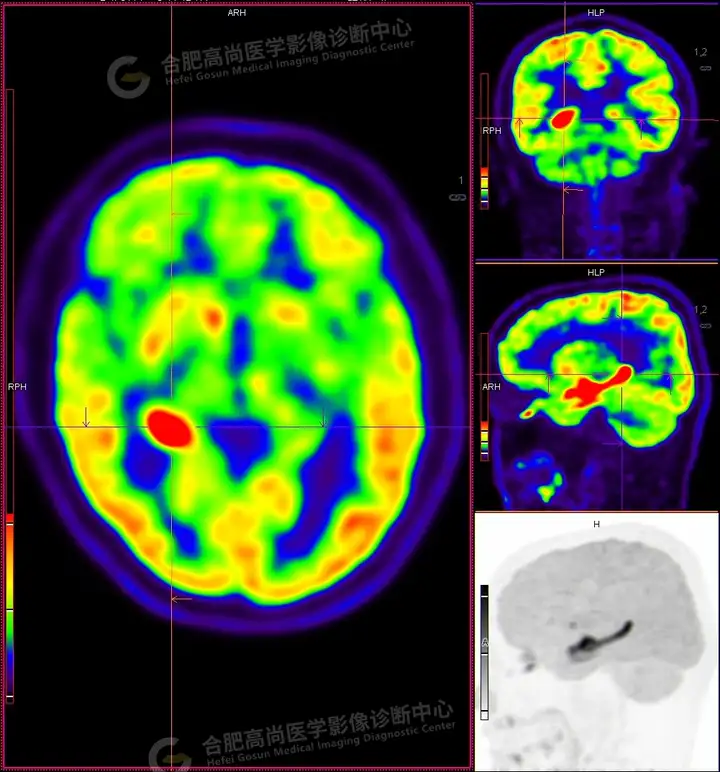

18F -FDG PET/CT检查图像:

18F -FDG PET/CT检查所见:

发作间期显像:PET显像双侧海马呈放射性摄取异常增高,以右侧明显,右侧海马SUVmax16.1、SUVavg4.4,左侧海马SUVmax7.3、SUVavg3.1(同层面额叶脑皮质SUVmax5.9、SUVavg2.3);CT示左侧海马体积较右侧似轻度缩小,左侧侧脑室颞角轻度增宽。PET显像右侧杏仁核及右侧基底节区局灶性放射性摄取异常增高,SUVmax14.1、SUVavg5.7(左侧SUVmax5.1、SUVavg3.6);CT示右侧杏仁核及右侧基底节区大小、形态正常,未见异常密度灶。

18F -FDG PET/CT检查结论:

发作间期显像:双侧海马、及右侧基底节区FDG代谢异常增高,考虑致癫灶可能大,请结合临床。